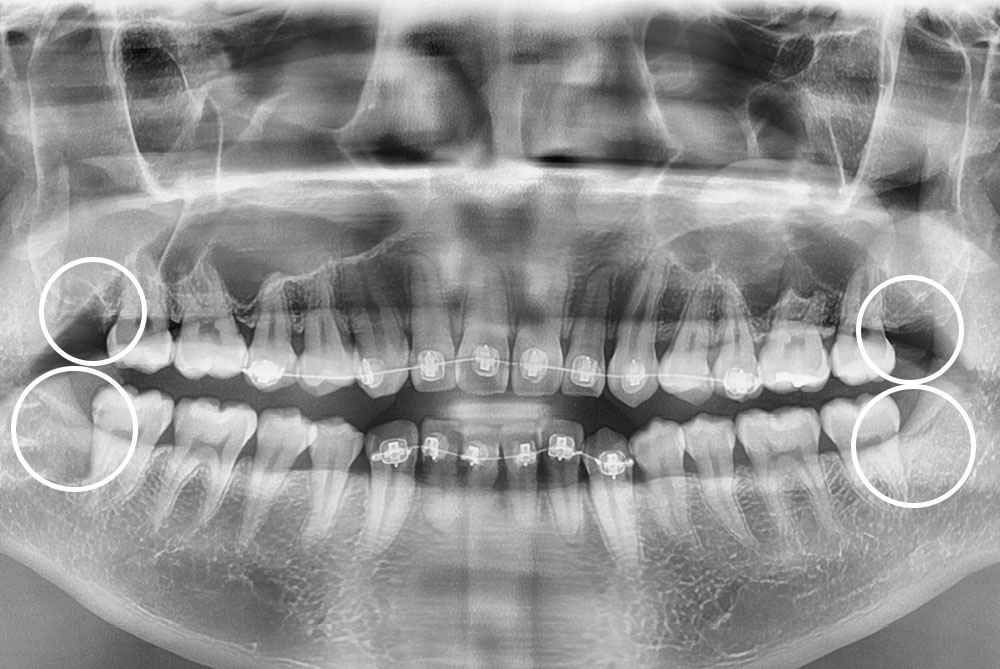

PX20211007_181619_0000_00004C5E.jpg

치료후 : 2021-10-07

세종치과는 구강악안면외과학 박사이신 원장님이 발치하는 치과입니다.